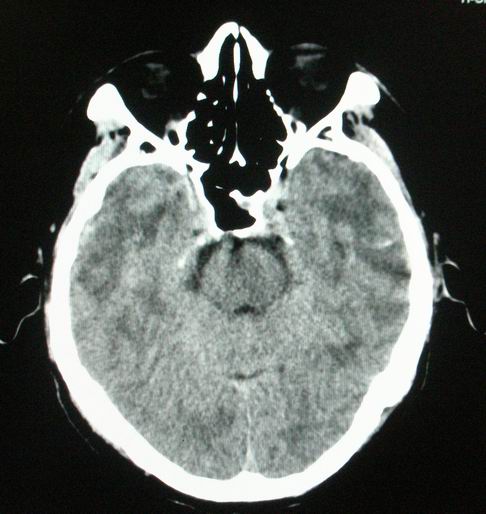

以下是引用随光逐影在2008-4-5 7:46:00的发言:[br]1)考虑为:多发性脑转移瘤。建议:行进一步检查。2)多发性腔隙性脑梗塞。3)脑白质病。4)脑萎缩。

以下是引用zjzjr在2008-4-5 9:00:00的发言:[br]1.双侧颞叶占位性病变,考虑为转移瘤可能性大。[br]2.左侧基底节区陈旧性腔隙性脑梗塞。[br]3.脑白质病。建议mri进一步检查。

以下是引用xuhuihong在2008-4-5 0:59:00的发言:[br]1.双侧颞叶占位性病变,考虑为转移瘤可能性大。[br]2.左侧基底节区陈旧性腔隙性脑梗塞。[br]3.脑白质病。建议mri进一步检查。

以下是引用形影不离在2008-4-4 23:29:00的发言:[br]1.双侧颞叶占位性病变,考虑为转移瘤可能性大。[br]2.左侧基底节区陈旧性腔隙性脑梗塞。[br]3.脑白质病。